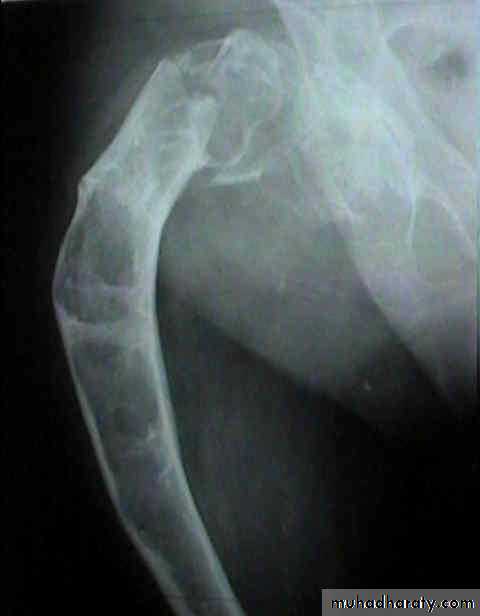

Developmental disorder whereby normal bone is replaced by fibrous tissue with flecks of osteoid.It may affect one bone (monostotic) or multiple bones (polystotic).

The lesion may be very large causes bone expansion and cortical thinning with progressive deformity and sometimes pathological fracture.Lesions occur in metaphysis & diaphysis, proximal femur is a common site it gives characteristic deformity called (shepherd’s-crock deformity(عصا الراعي.

X-ray shows lucent cystic lesion sometimes large and multilocular with bone expansion and cortical thinning it contains multiple calcific spots giving the ground-glass appearance, there is always possible deformity or pathological fracture.